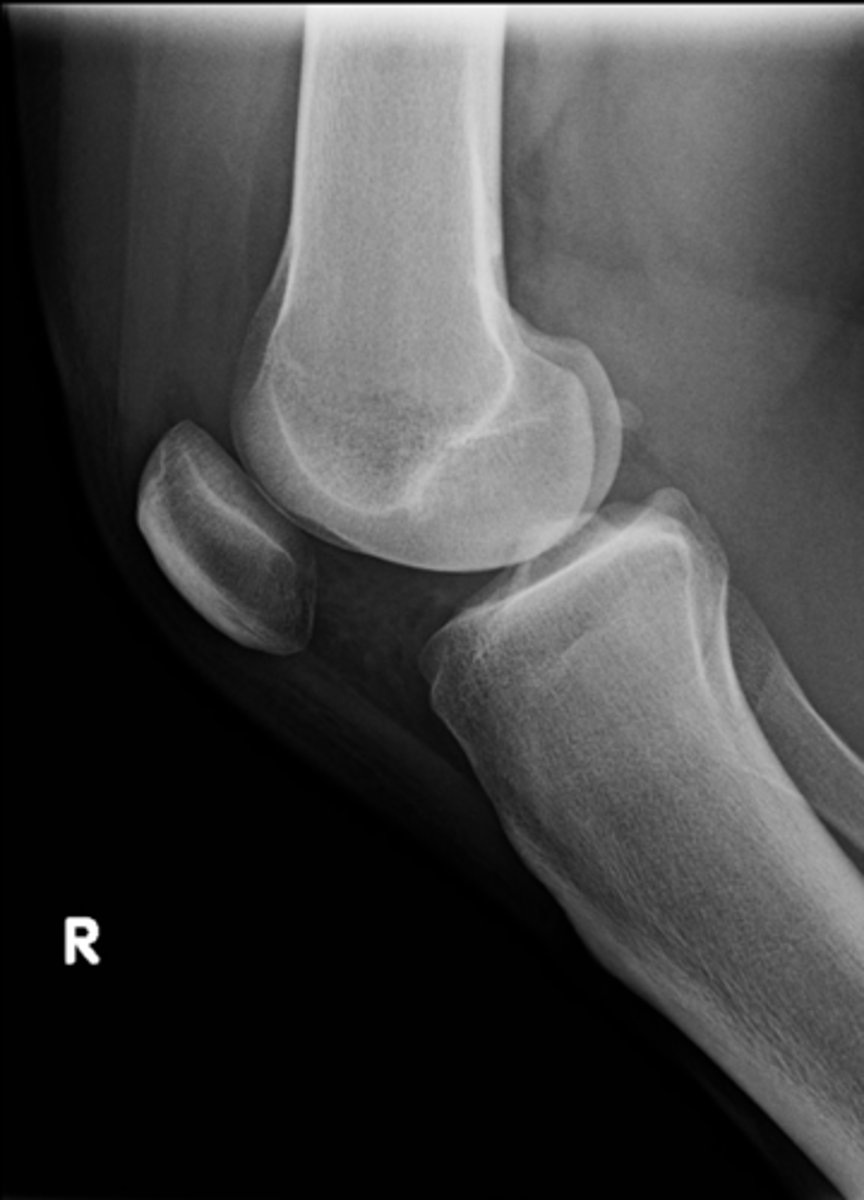

Lateral knee

ID standard knee projection

Flexion

Lateral knee projections are generally taken with _____